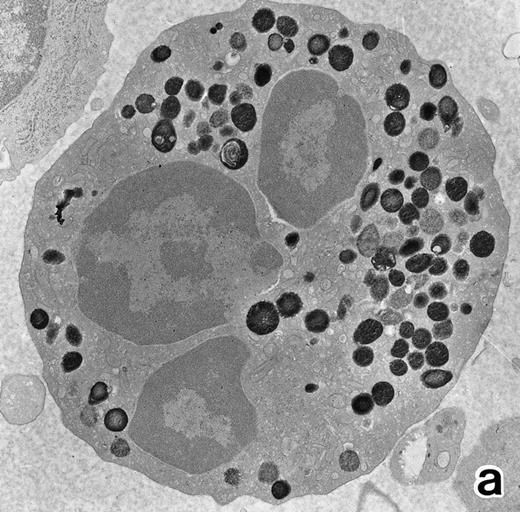

(a) A PMN in patient no. 2 after 10 days of ATRA treatment. The nuclei are irregularly lobulated, with some of them being connected by nuclear filamentous structures, and heterochromatin is condensed along the nuclear membrane. (Original magnification × 13,100.) (b) Higher magnification of a portion of the cell in (a). The cytoplasmic granules are large and spherical, and some of them contain flocculent material and central cores with higher electron density. (Original magnification × 20,200.)